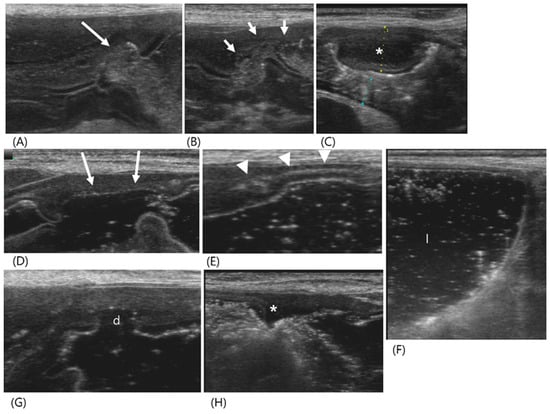

2.2. Case 2